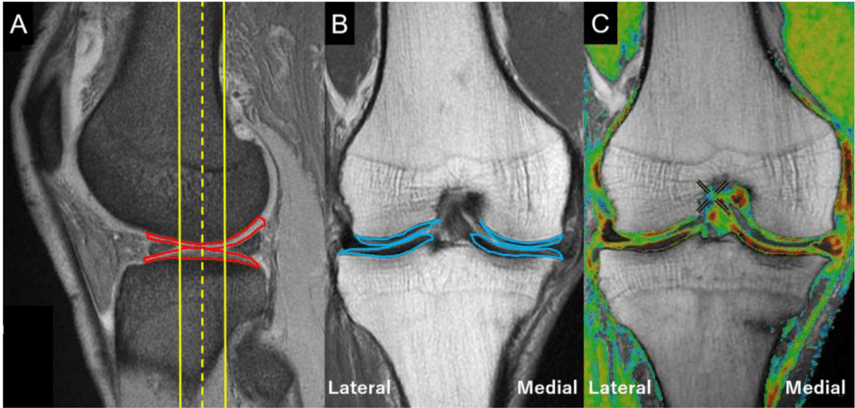

Microfragmented Adipose Tissue Associated With Collagen Membrane in the Treatment of Focal Knee Cartilage Defect

Daniel Peixoto Leal, Henrique Fuller, Bruno Butturi Varone, Andre Giardino Moreira da Silva, Marco Kawamura Demange, Riccardo Gomes Gobbi, Luis Eduardo Passareli Tirico, Arthroscopy Techniques, 2024